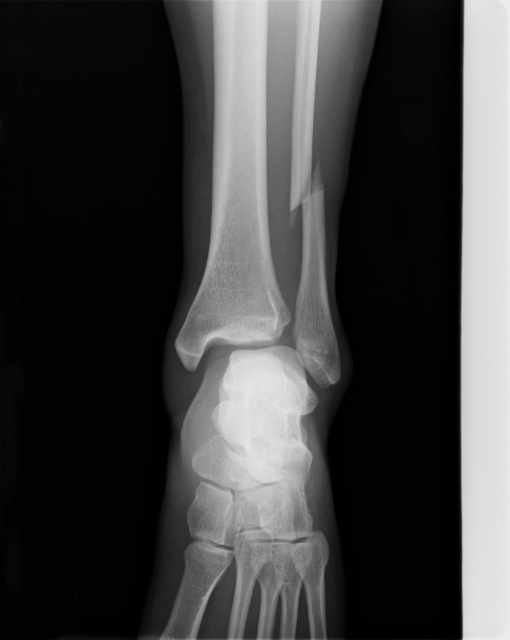

일단 구획증후군의 경우 급성과 만성의 경우로 나누어지고 있습니다. 급성의 경우 매우 응급상황이며 골절이나 충돌 부상(자동차 사고 등)과 같은 심각한 부상 후 발생하게 됩니다. 해당 사항의 경우 구획 증후군의 가장 흔한 원인 중 하나이며, 팔과 다리의 구획 내에서 출혈이나 부종을 유발하게 됩니다. 이 부종은 구획의 압력을 증가시키고 구획증후군으로 발전하게 됩니다. 또한 충돌 부상과 같은 자동차 사고나 팔다리에 무거운 물체가 떨어져서 발생하는 경우 근육과 혈관에 심각한 외상을 일으키게 되는데 이는 후속 부종과 출혈로 이어지고, 급격한 압력의 증가를 유발해 해당 질병을 유발하게 됩니다. 이외에도 화상 및 압박붕대를 사용하게 되는 경우에도 발생할 수 있습니다. 만성의 경우는 특정 근육을 반복해서 사용하는 운동선수에게서 흔히 생기게 될 수 있습니다. 또한 일반인의 경우 말아톤(달리기), 자전거 라이딩을 하는 경우에도 특정 부위에 압력이 증가하여 구획증후군을 발생시킬 수 있습니다. 이외에도 특정 약물 사용이나 감염등을 통해서도 원인이 되기도 합니다.